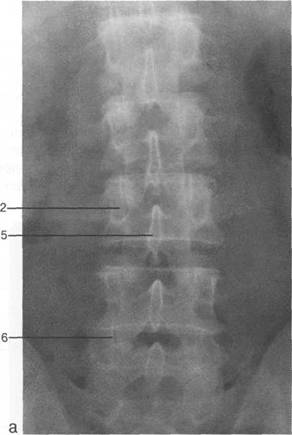

L, L,j,

L1V v

S,; L1V.

L^.

L{ Ln